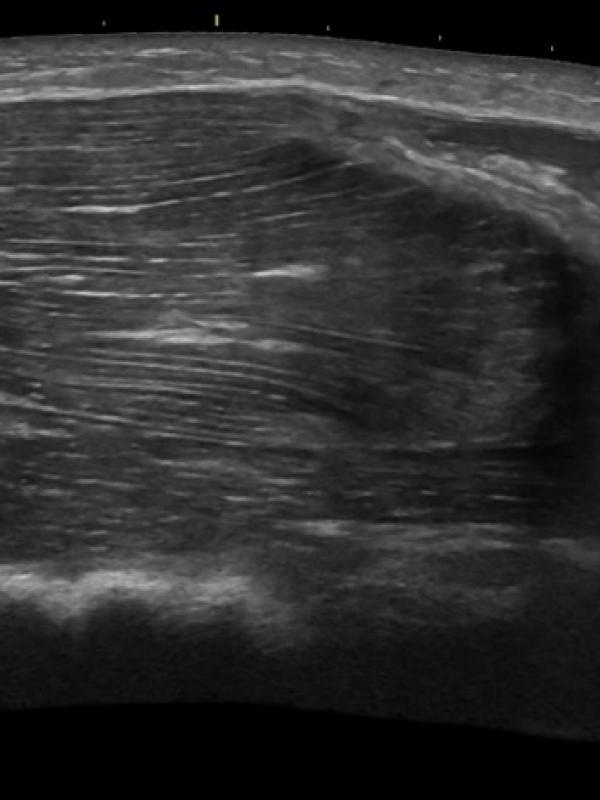

Musculoskeletal ultrasound (MSK)

Ultrasound imaging of tendons, ligaments, and muscle groups. Referring providers order musculoskeletal ultrasound for a number of reasons. Some common reasons are: suspicion of muscle or ligament/tendon tear or damage, trigger finger or lump.